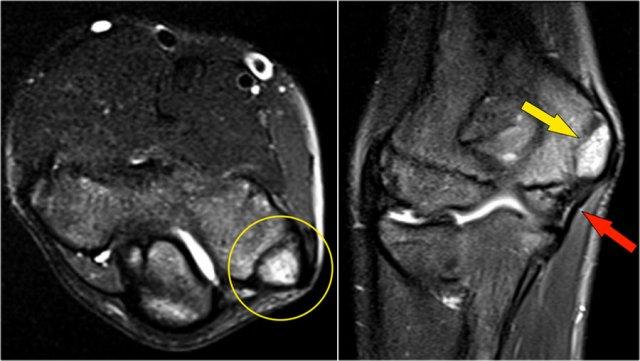

Những hình ảnh này của một cầu thủ bóng chày trẻ, xuất hiện với triệu chứng đau khuỷu tay lúc 14 tuổi.

Hình ảnh T2W-fatsat cho thấy phù tủy xương và có thể có gãy xương dưới sụn.

Rõ ràng là có người đã bảo cậu bé tiếp tục ném bóng, vì cậu quay lại ba năm sau khi 17 tuổi và bạn có thể thấy điều gì xảy ra khi người ta thúc ép quá mức để biến những đứa trẻ này thành vận động viên chuyên nghiệp.

Hình ảnh T1W cho thấy sự phân mảnh (mũi tên vàng) với một mảnh xương tự do (mũi tên đỏ).

Hình ảnh T2W chứng minh rằng mảnh xương không ổn định do có tín hiệu cao giữa mảnh xương và xương cánh tay.

Khi nội soi khớp, có thể thấy sự lõm xuống và không đều của sụn chỏm con.

First the loose bodies were taken out.

Sau đó, thủ thuật OATS thường được thực hiện, mà chúng ta sẽ thảo luận ngay bây giờ.